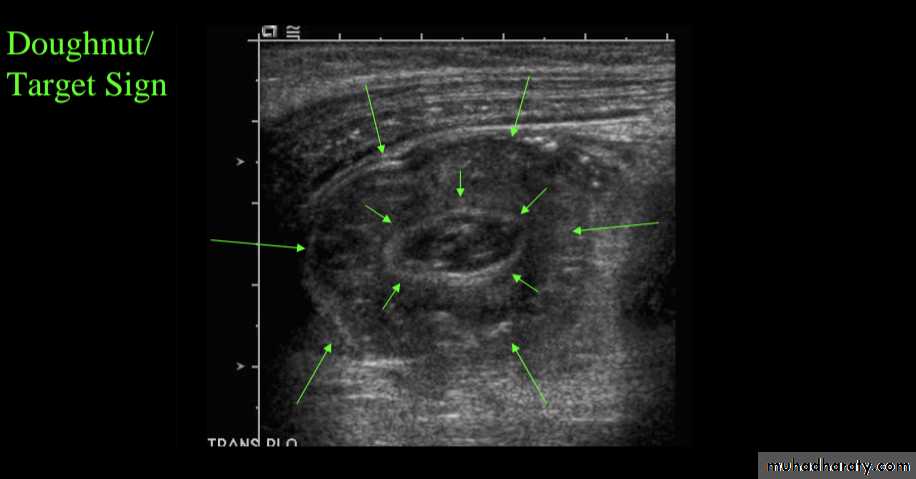

Ultrasound

is a reliable screening tool for children at low risk for intussusceptionsUltrasound signs include:

target sign (also known as the doughnut sign)

Pseudo kidney shape sign